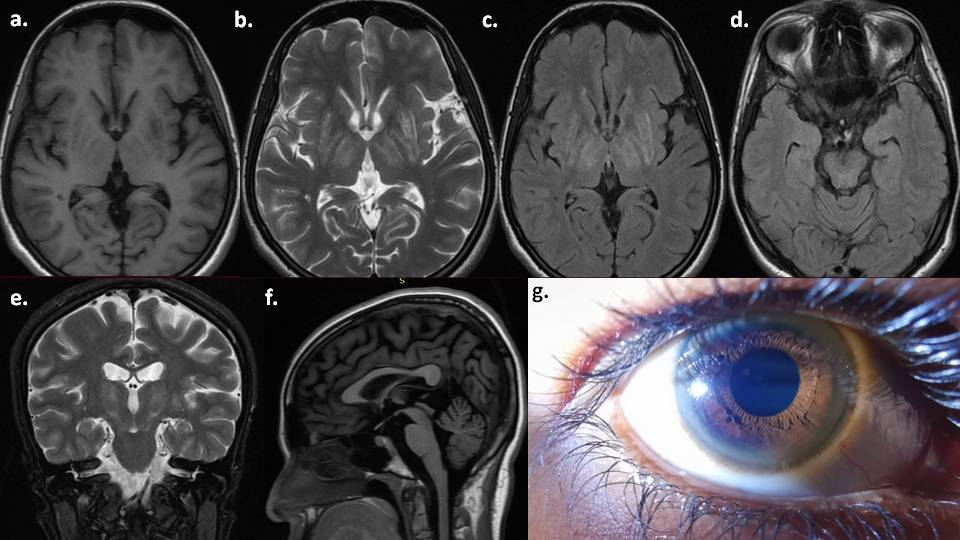

حلقات كايزر-فلايشر وإعتام عدسة العين على شكل زهرة عباد الشمس

سيقوم طبيبك أيضًا بفحص عينيك بحثًا عن حلقات كايزر-فلايشر (K-F) وإعتام عدسة العين على شكل زهرة عباد الشمس. حلقات كايزر-فلايشر هي تغيرات لونية غير طبيعية في العين، تتراوح بين الذهبي والبني، وتنتج عن ترسبات النحاس الزائد. تظهر حلقات كايزر-فلايشر لدى حوالي 97% من المصابين بداء ويلسون.

أما إعتام عدسة العين على شكل زهرة عباد الشمس، فيظهر لدى واحد من كل خمسة مصابين بداء ويلسون. وهو عبارة عن مركز متعدد الألوان مميز، تتفرع منه شعاعات خارجية.

الفحوصات التصويرية

قد تساعد فحوصات التصوير بالرنين المغناطيسي (MRI) والتصوير المقطعي المحوسب (CT) في الكشف عن أي تشوهات في الدماغ، خاصةً إذا كنت تعاني من أعراض عصبية. لا تشخّص هذه الفحوصات الحالة المرضية، ولكنها تساعد في تحديد التشخيص أو مدى تقدم الحالة.

سيبحث طبيبك عن إشارات ضعيفة في جذع الدماغ وتلف في الدماغ والكبد.